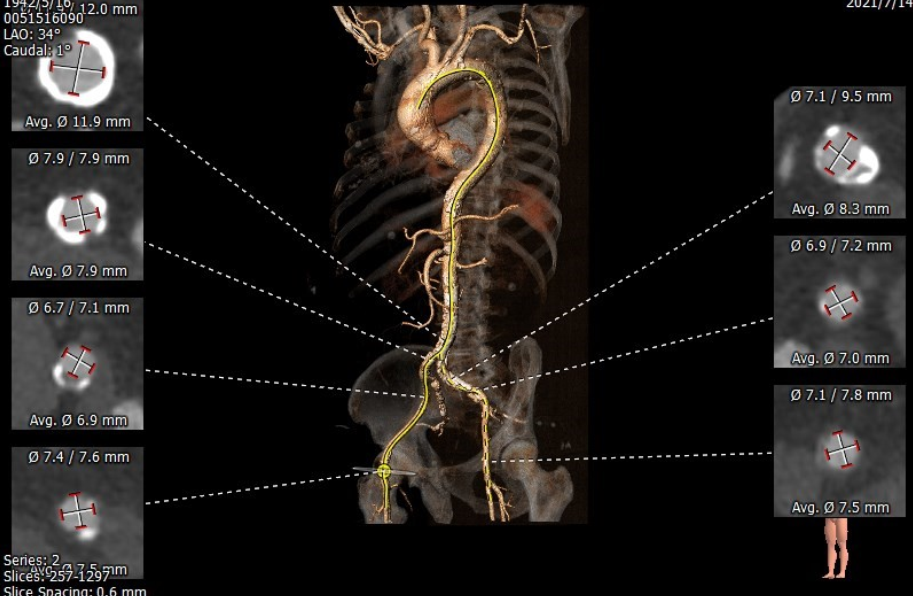

“All in one”技术示意:将瓣膜输送器与5F造影猪尾导管同时置于20F鞘管中

术前评估:

Annulus 22.6*27.5mm Perimeter=78.8mm

SOV 27.1*27.0*27.2mm

STJ 28.0*32.1mm

LVOT 21.5*28.7mm Perimeter=78.5mm

Ascending Aorta 38.7*40.1m

内径符合TAVI要求

该患者CT特点为:

功能性二叶瓣,左右融合,钙化集中于无冠窦,长条状钙化自瓣上延续至二尖瓣前叶,冠脉开口高度可,腹主动脉至髂动脉多发钙化,内径可,拟右股动脉入路,22mm球囊扩张,植入VitaFlow 27。